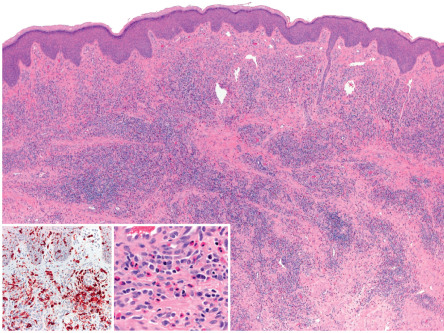

Histologic features suggestive of a bite or sting include the presence of a wedge-shaped perivascular lymphocytic infiltrate with eosinophils, endothelial prominence, and overlying spongiosis or focal epidermal necrosis. Marked spongiosis can result in blister formation, and Langerhans cell hyperplasia may be evident ( Fig. 85.3 ).